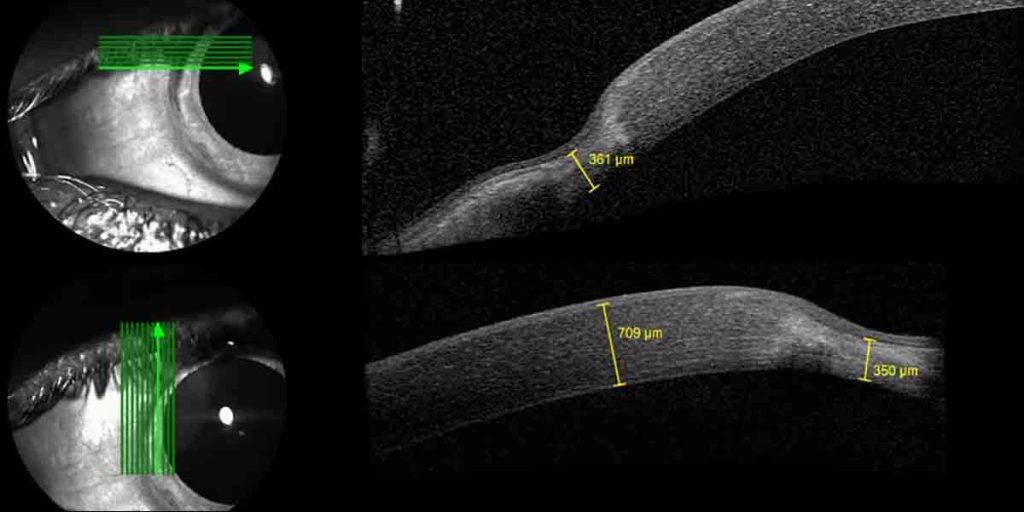

This OCT image shows a thinning of the cornea at the periphery (the edges) of the cornea)